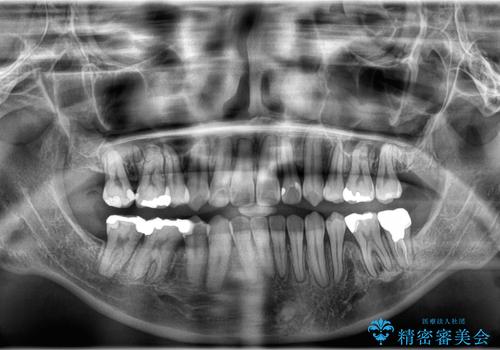

- 開咬と歯のデコボコ(叢生)、八重歯を主訴にご来院された患者様です。

矯正の精密検査の結果、上顎左右4番および下顎左右5番の計4本を抜歯し、ワイヤー矯正(クリア装置)にて治療を行いました。

虫歯があったので、虫歯治療は矯正前に行っています。